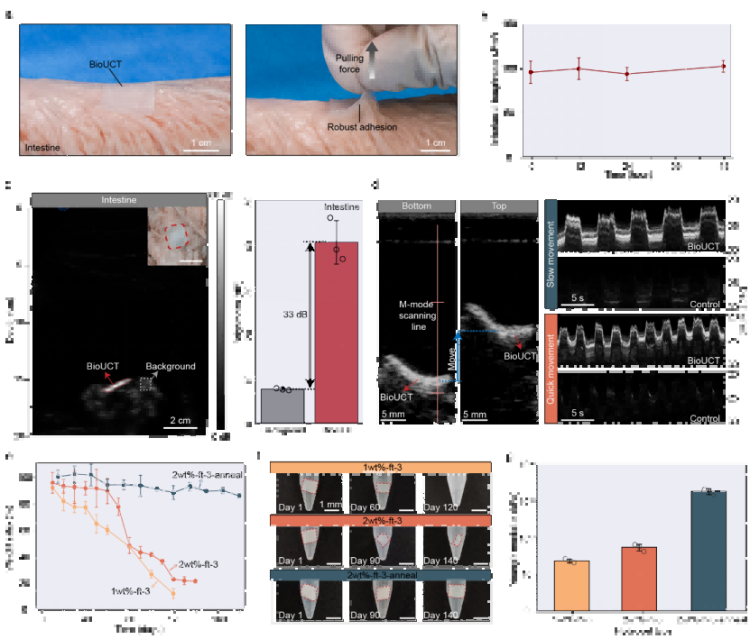

①革命性成像性能:從“看不見”到“高清追蹤”超強聲學反射(圖2a-b)通過周期性微氣囊設計,BioUCT在體外測試的2MHz超聲下實現57dB頻譜信號增幅(較普通水凝膠),在實際動物實驗中將B超圖像亮度提升30dB,使腸道輪廓清晰顯現(圖2b)。時/頻域分析顯示其回聲強度遠超軟組織(圖2a),解決了腸道超聲的信噪比受腸道“弱反射”限制的核心痛點。

抗形變穩定性(圖2f-g)在50%拉伸及90°彎曲狀態下(模擬腸道蠕動),B超/M超成像亮度波動<5%(圖2f),相位監測波形穩定(圖2g),確保動態監測可靠性。

大角度成像能力(圖2c-e)探頭在深度(5-25cm)、角度(±30°)、水平位移(±20mm)變化時,圖像亮度標準差<1.5dB(*n*=3),適配臨床操作誤差。

圖2. BioUCT的超聲對比成像性能。

② 智能生物適配:像“第二層生物表皮”一樣工作強力粘附與抗脫落(圖3a-b)離體豬腸實驗證實,BioUCT與腸壁界面韌性達200 J/m2(相當于外科縫合強度),48小時內粘附穩定性>95%(圖3b)。拉力測試中可承受10N以上牽拉(圖3a),遠超腸道蠕動產生的生理應力(通常<2N)。

精準降解調控(圖3e-g)通過調節PVA/CMC水凝膠結晶度,實現10%-90%的可控降解速率(120天內),且降解過程中楊氏模量保持15-35kPa(圖3g),始終匹配軟組織力學特性,避免器官損傷。

圖3. BioUCT的離體展示。

③ 離體驗證臨床價值:動態追蹤不再是難題顯著提升診斷靈敏度(圖3c-d)貼附BioUCT的離體豬腸在B超圖像中亮度提升33dB(圖3c),相當于將傳統超聲的“模糊陰影”變為“高清影像”。M超動態成像成功捕捉模擬腸蠕動軌跡(圖3d),為量化腸道運動提供新工具。跨器官普適性(補充圖18)在豬心、胃等器官同樣實現>30dB亮度提升,證實技術可擴展性。